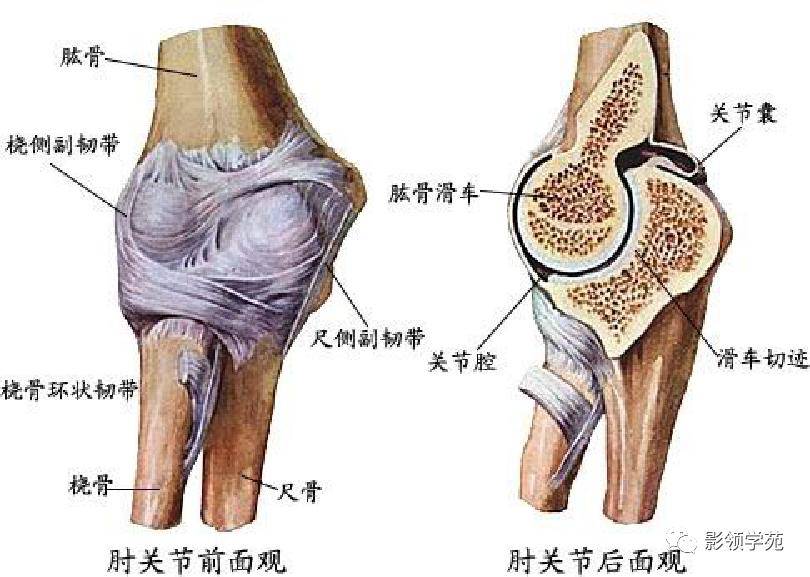

关节与韧带系统

关节与韧带系统